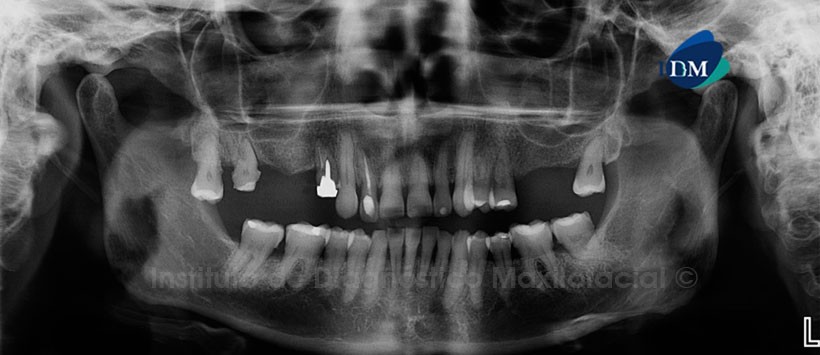

En la radiografía panorámica (Figura 1) se aprecia múltiples restauraciones, extrusión de pieza 18, obturación de conductos en piezas 14 y 12, así como la preparación coronaria y ensanchamiento del espacio periodontal en la pieza 17.